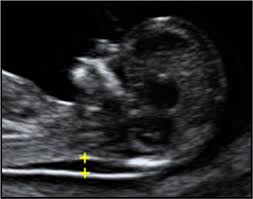

Antenatal Soft Markers On Ultrasound Radiology Reference Article Radiopaedia Org